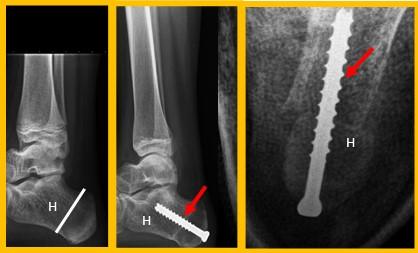

Calcaneus osteotomie

Bij een calcaneus osteotomie wordt het hielbot doorgezaagd en meer naar de buitenzijde verplaatst. De achtervoet komt zo meer van de “O” positie in een “X” positie.

Het vastzetten van beide botdelen gebeurt meestal met een schroef vanuit de hiel, middels een apart litteken.

Figuur 1: Voorbeeld van een calcaneus osteotomie. H=hielbot (calcaneus). De witte streep op het linker plaatje is de locatie van het litteken. De Rode pijl wijst naar de schroef. Op het meest rechtse plaatje zie je de verschuiving van het hielbot naar de buitenzijde